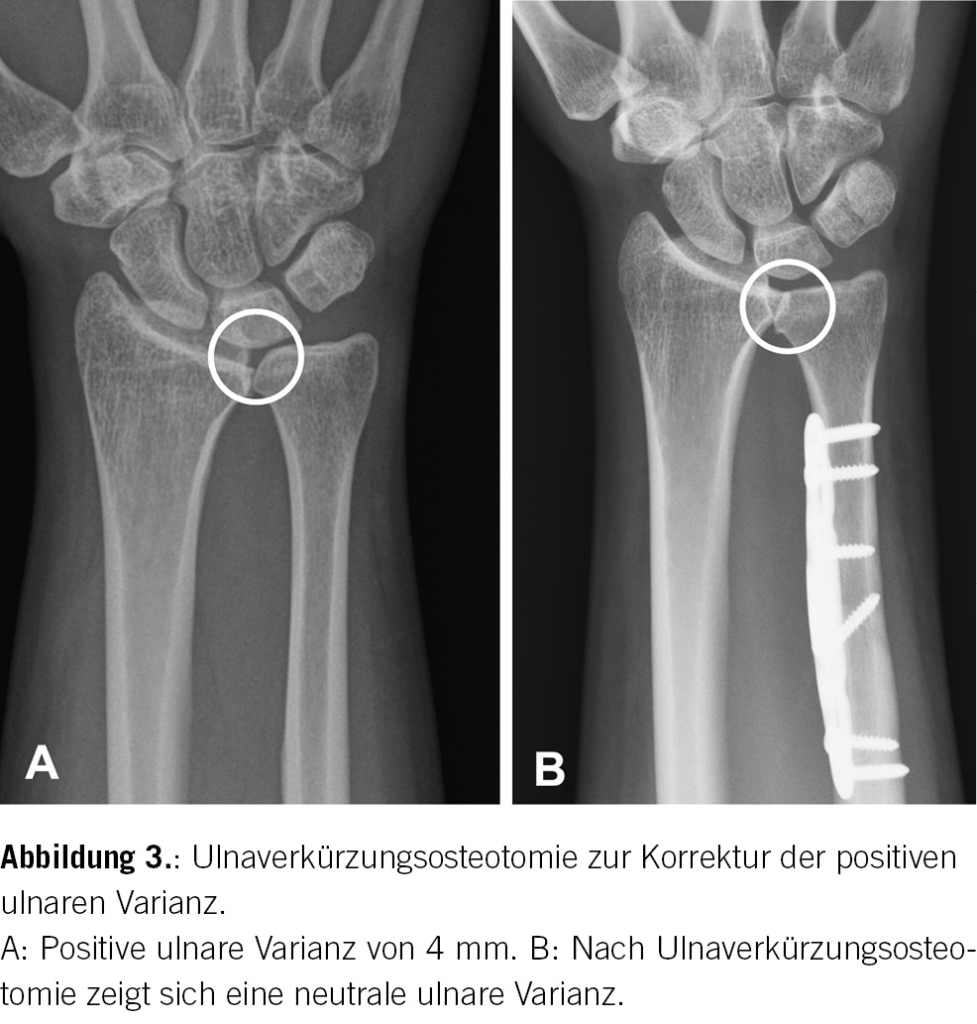

Es bleibt nun das weitere Vorgehen festzulegen. Bei starken Schmerzen können eine Ruhigstellung und analgetische Therapie für ein bis zwei Wochen sinnvoll sein. Eine intraartikuläre, unter Röntgenkontrolle durchgeführte Kortisonspritze ist ebenfalls eine gute Option zur Linderung starker Schmerzen. Meist sind dies jedoch keine Dauerlösungen, da das Grundproblem nicht beseitigt wird. Bei unserer Patientin erfolgte deshalb eine Arthroskopie zum Débridement des TFCC und einer lokalen Synovektomie sowie eine offene Ulnaverkürzungsosteotomie von 4 mm zur Entlastung des ulnokarpalen Kompartimentes (Abb. 3). Dies führte zu einer Beschwerdefreiheit bei sämtlichen Tätigkeiten innerhalb von sechs Monaten.

Das ulnokarpale Impaktionssyndrom kann primär aufgrund einer anlagebedingten positiven ulnaren Varianz oder posttraumatisch auftreten, i.d.R. wenn der Radius nach distaler Fraktur in Verkürzung abheilt. Die ulnokarpale Gelenkspalt-Verschmälerung führt zu einer erhöhten Belastung des dazwischen liegenden TFCC. Dies kann mit der Zeit zu einer zentralen TFCC-Läsion und zu einem Knorpelschaden am Os lunatum und am Ulnakopf, später auch zu luno-triquetralen Bandläsionen führen [1]. Die Patientinnen und Patienten beschreiben entweder langsam zunehmende oder nach einem bestimmten Ereignis (Sturz, Schlag, etc.) rasch auftretende ulnare Handgelenksschmerzen. In der klinischen Untersuchung zeigen sich Schmerzen typischerweise in Ulnarduktion und Extension im Handgelenk, da dabei das ulnokarpale Kompartiment komprimiert wird (Ulnocarpal Stress Test) [2]. Zur weiterführenden Diagnostik sollte zunächst eine konventionelle Röntgenaufnahme mit Bestimmung der ulnaren Varianz durchgeführt werden. Bestätigt sich eine positive ulnare Varianz, sollte bei entsprechenden Beschwerden eine Überweisung an eine Handchiurgin oder einen Handchirurgen erfolgen, wo die Entscheidung bzgl. weiterer Abklärungen (MRT) und Therapie erfolgen kann. Eine Ulnaverkürzungsosteotomie ist bei vorliegender Ulna-Plus-Variante das therapeutische Mittel der Wahl, um die Kraftverteilung im Handgelenk wieder zu normalisieren [3].